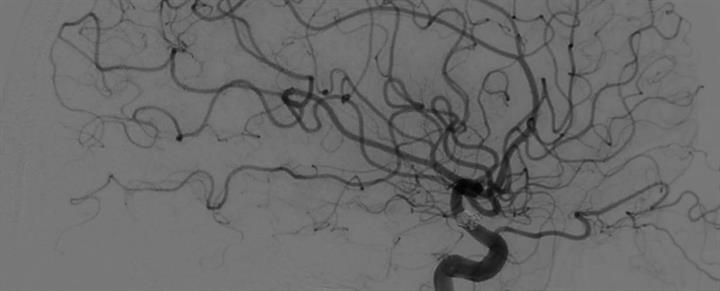

Επειδή το περιστατικό είναι σοβαρό και ακούω καθημερινά ακόμη και νέους ανθρώπους είτε να φεύγουν από τη ζωή από αυτό το περιστατικό, είτε να περνάνε το ίδιο με καλά ή όχι αποτελέσματα, σκέφτηκα να δημοσιεύσω την επί 32 ετών προσωπική μου εμπειρία πάνω στο θέμα.

Έτσι, ίσως δώσουμε σε κάποιους ανθρώπους το εναύσμα να παρακολουθούνται ακόμη και από μικρές σχετικά ηλικίες, πάνω σε ιατρικά θέματα.